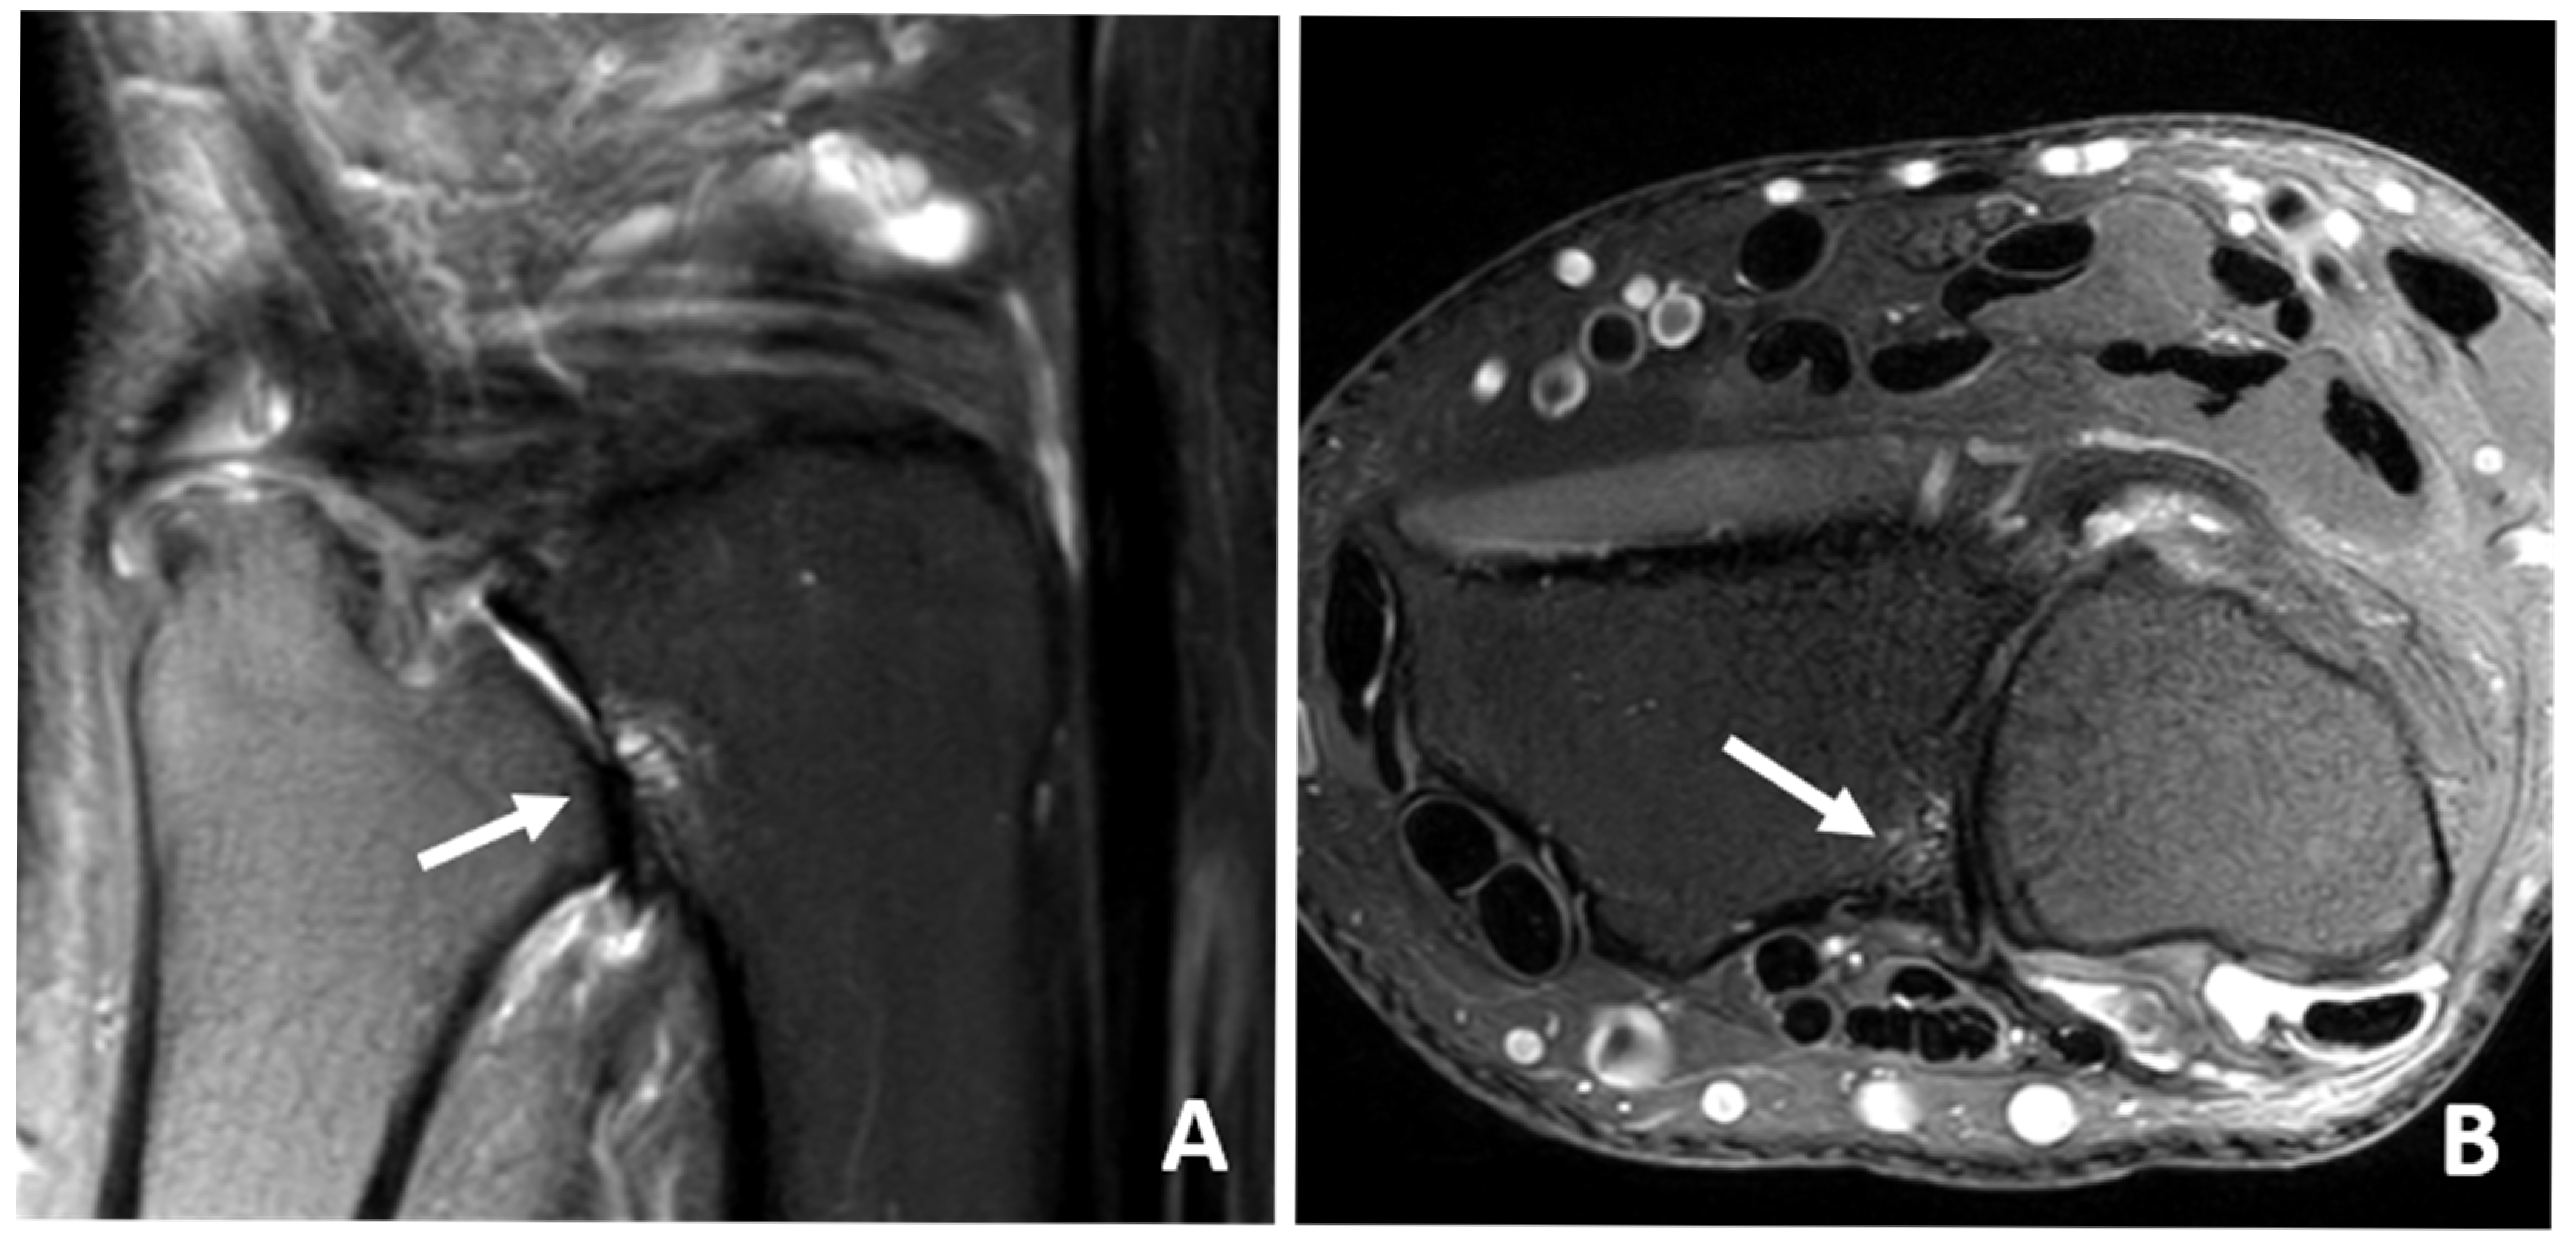

3.4. MRI Scan